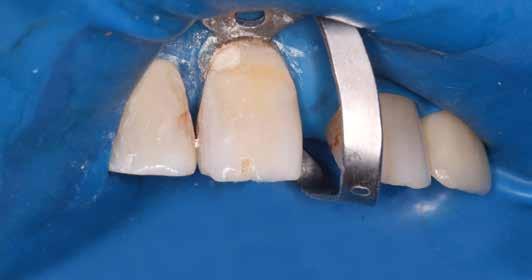

Gyökérkezelendő posterior fogak esetén gyakran találkozunk mély, szubgingivális szuvassággal az approximális területen, melynek szanálása elengedhetetlen előfeltétele a fog endodonciai kezelésének. Az így kialakuló, már kitisztított üreg restaurálása gyakran nehezen kezelhető szituációt teremt a klinikai gyakorlatban. Ezt sokan „endodonciai csonkfelépítésként” kezelik, mely magában rejthet egy ideiglenes jelleget is, holott ez teljesen téves irány. A jelenlegi modern angol nómenklatúra, azaz a „Deep Margin Elevation (DME)” sokkal jobban tükrözi a beavatkozás célját és nehézségét is. Ugyanis a DME a legnehezebb körülmények között elvégzendő adhezív beavatkozásnak minősül. Emellett a teljes, végleges restaurátum sikerességét meghatározza, és kulcsfontosságú a fog megtarthatóságának eldöntési folyamatában: „ha nem tudjuk megfelelően elvégezni, ugyan hogyan akarjuk most vagy a későbbiekben kezelni és megtartani az érintett fogat?” Előadásomban szeretnék bemutatni egy a jelenlegi szakirodalmon alapuló modern, könnyen kivitelezhető protokollt és néhány trükköt, amelyek megkönnyíthetik és kiszámíthatóbbá tehetik ezeknek az erősen destruált fogaknak a helyreállítását.

Kofferdám: ellenség vagy barát?

Véleményem szerint az abszolút izolálás elengedhetetlen kelléke a mai modern fogászatnak. Az izolálás ezen formája – számos előnyének köszönhetően – segítséget tud nyújtani mind az endodoncia, mind pedig a resturatív fogászat területén. Az előadásom fő célja, hogy meghozzam a kedvet a kofferdám használatához. Megerősítést szeretnék adni azoknak is, akik alkalmazzák, de bizonytalanok. Emellett tippekkel és trükkökkel is fogok szolgálni a hozzám hasonló fanatikusok számára, ezzel megkönnyítve a nehezebb esetek izolálását is.

A megfelelő vizuális kontroll és az izolálhatóság kedvéért lebenyt alakítottunk [4. kép]. Így az abszolút izolálás már kivitelezhető volt és kofferdám izolálásban kezeltük a léziót [5. kép]. Mivel az elváltozás nem látható területen helyezkedett el, illetve a kavitás kis kiterjedését figyelembe véve kalcium-szilikát bázisú anyagot választottunk a restauráláshoz (Biodentine, Septodont) [6. kép]. Miután letelt a választott anyagunk kötési ideje (12 perc), zártuk a lebenyt [6. kép]. Páciensünk azóta is panaszmentes, kétéves kontrollon állapota rendben volt [7. és 8. kép].